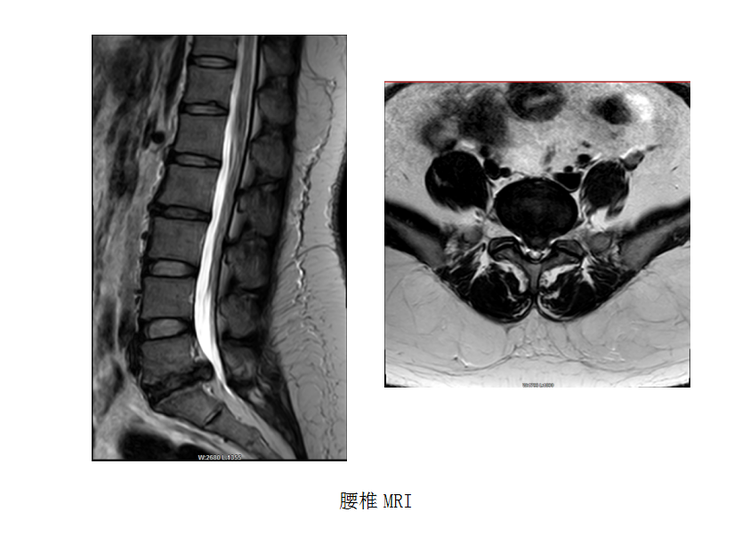

患者,女,28歲,主因“行走時(shí)左下肢抽痛1個(gè)月”入院。腰椎MRI檢查示:腰5骶1椎間盤變性并突出 ,腰5骶1椎體輕度骨質(zhì)增生并終板炎,腰背部皮下肌筋膜炎。